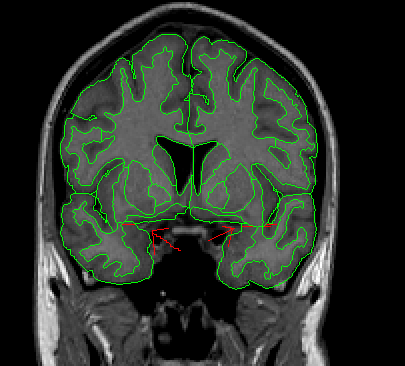

The insular cortex is “hidden” between the temporal and inferior parietal corticies. By drawing sulci lines in the sagittal view, we gain an outline of it in the coronal. Choose a sagittal slice where insula is clearly visible (Fig 1), then draw a “circle” around it (Fig 2). Do this for several slices and for both hemispheres.

Figure 1              Figure

2

Once you have drawn your sulci lines, the insula should be clearly outlined (by little dots) in the coronal view (Fig 3). This is particularly useful in the more anterior slices.

Figure 3